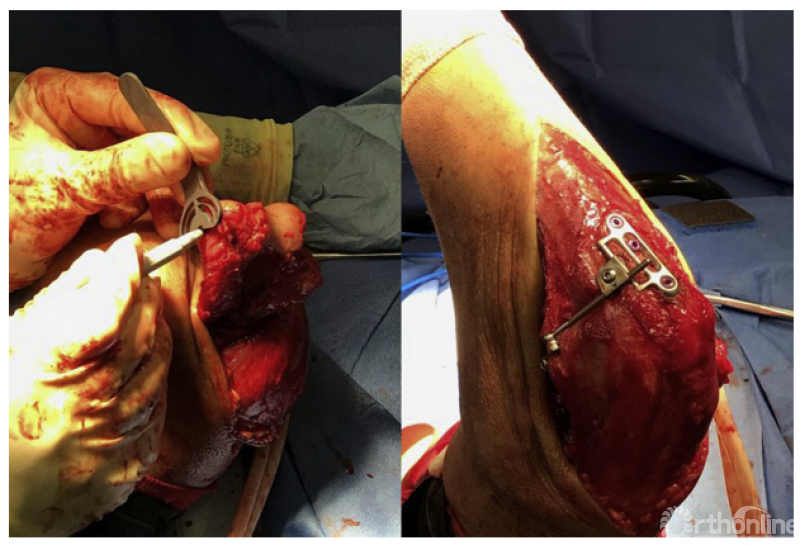

3、难以手术重建的冠状突骨折以及冠状突缺损导致的陈旧肘关节不稳定,既往有髂骨、鹰嘴、桡骨头、肋骨、异体骨等,甚至还有冠状突假体。Wegmann等通过三维空间影像学测量和配准,发现采用健侧鹰嘴尖50°截骨的骨块,和原始冠状突的形态最贴合,尤其是关节面部分,这也为今后重建冠状突提供了一种可行的解决方案。